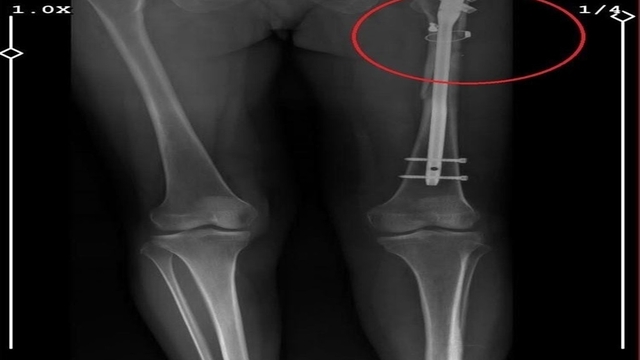

Osmangazi ilçesi Küplüpınar Mahallesi'nde 2023 Haziran ayında meydana gelen olayda; İlyas Sarıkaya, mahalleden arkadaşı Recep Özaslan'ı, Alzheimer hastası annesi A.S. ve sevgilisi Fatma O. ile birlikte yaşadığı eve çağırdı. İddiaya göre; uyuşturucu etkisinde olan Sarıkaya, sevgilisiyle ilişkisi olduğunu düşündüğü Özaslan'ı tabancayla vurdu ardından da 'acı çekmesin' diye 2 kez daha ateş etti. Özaslan, beline ve göğsüne isabet eden kurşunlarla hayatını kaybetti.

İlyas Sarıkaya, sevgilisi Fatma O.'yu da 8 kurşunla vurup, yaraladı. Arkadaşı Özaslan'ın cesedini önce çarşafa sonra da streç filme sarıp bantlayan Sarıkaya, eczaneden aldığı sargı bezi ve ilaçlarla pansumanını yaptığı sevgilisine yaralı haldeyken 21 gün boyunca cinsel saldırıda bulundu.